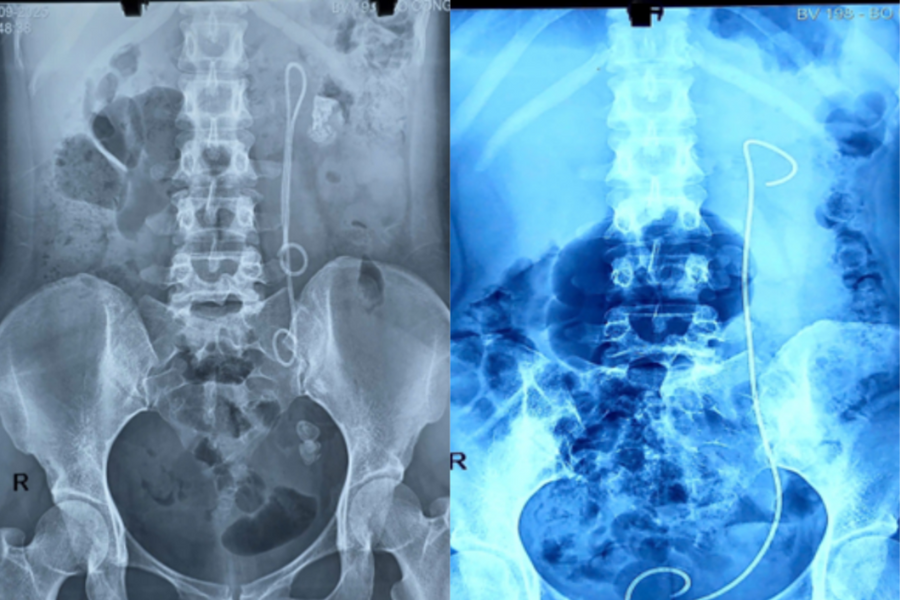

Nữ bệnh nhân bị bỏ quên thiết bị y tế trong cơ thể suốt 15 năm

Nữ bệnh nhân đi khám vì đau vùng thắt lưng kèm tiểu buốt, mới tá hoả vẫn còn một thiết bị y tế bị bỏ “quên” trong cơ thể suốt 15 năm qua.